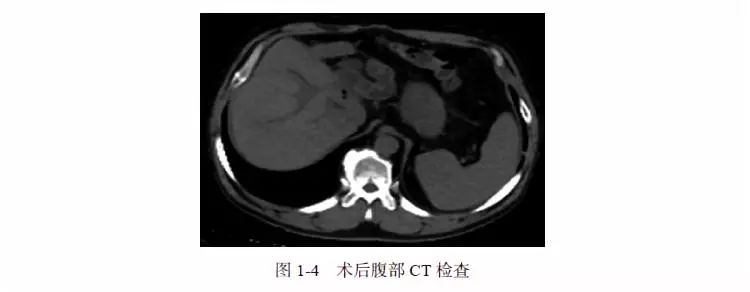

术后第15 天,血清学结果显示IgG4 13.40g/L(正常值0.03 ~ 2.01g/L)、IgG 27.2g/L。根据国际AIH 小组关于AIH 评分标准,该患者评分达17 分,可明确诊断为IgG4 相关性硬化性胆管炎(IgG4-SC)和IgG4 相关性自身免疫性肝炎(IgG4-AIH),遂给予泼尼松40mg/d 口服,4 周。患者皮肤、巩膜黄染和皮肤瘙痒症状消失。肝功能和CA19-9 降至正常范围。复查腹部CT 显示右肝管十二指肠吻合术后,肝内胆管正常(图1-4)。此后患者长期口服维持量的泼尼松(10mg/d)。随访6 个月期间患者病情无复发,无糖皮质激素不良反应。